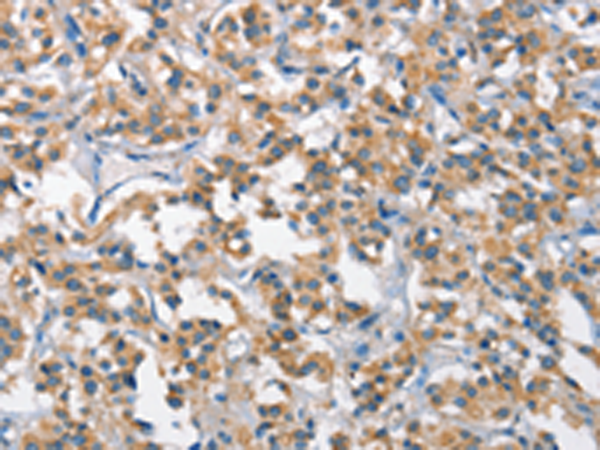

分类: 科研抗体货号: P07363别名: AILIM; CD278; CVID1应用: IHC反应种属: Human